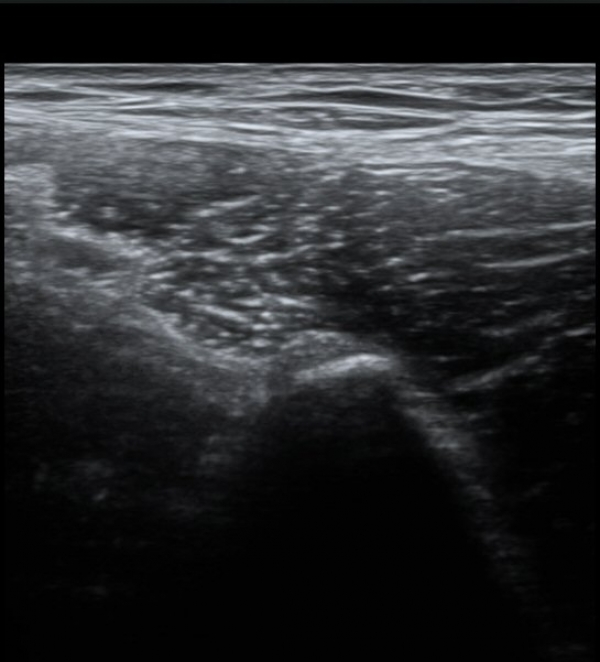

ŽÃËÀÚ¸¦ Á¶±Ý ³»ÃøÀ¸·Î À̵¿ÇÏ´Ï ÈûÁÙÀÇ °í¿¡ÄÚ°¡ ¼Ò½ÇµÇ¾î º¸ÀδÙ(»çÁø 2, 3)